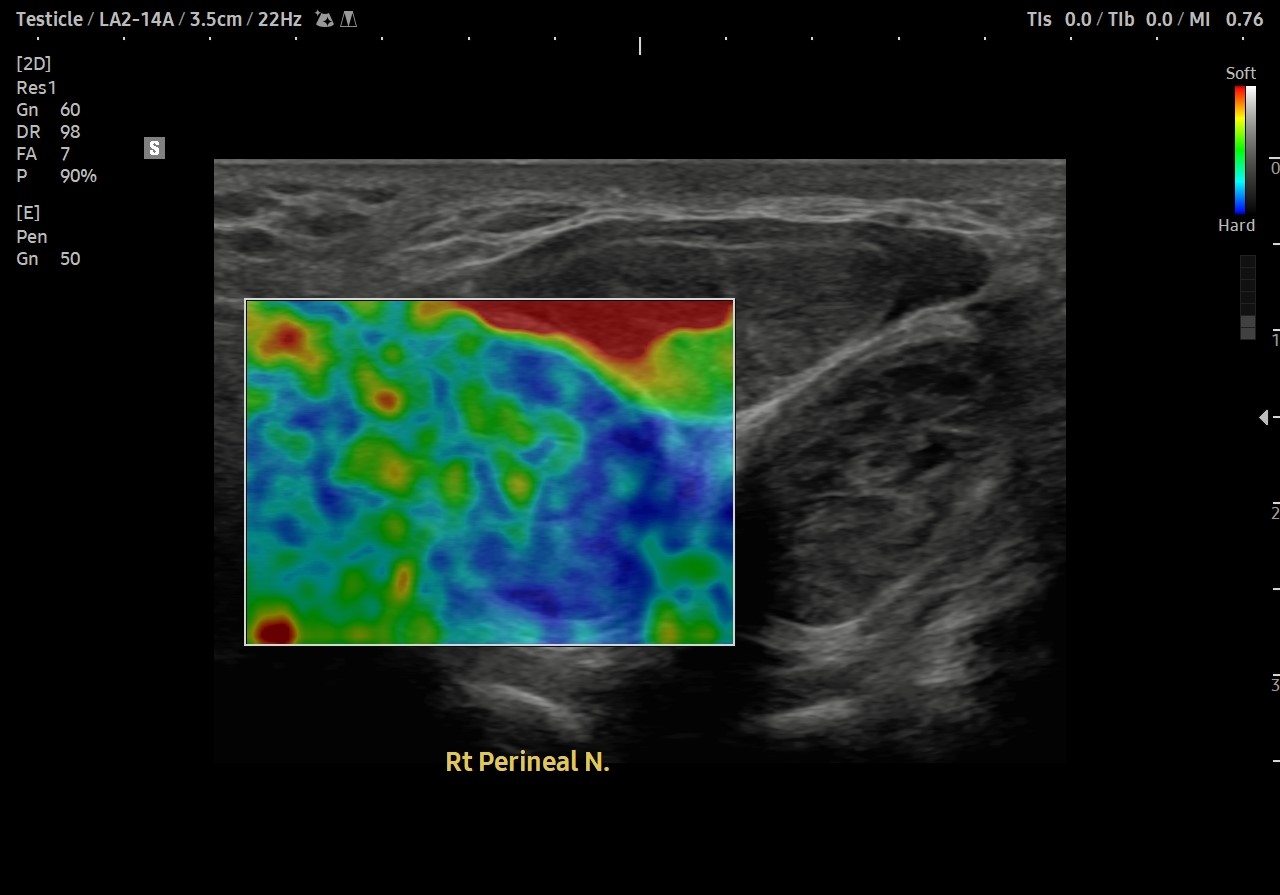

통증 부위를 살펴볼까요?

회음부의 통증과 치골부위 통증이 심했습니다.